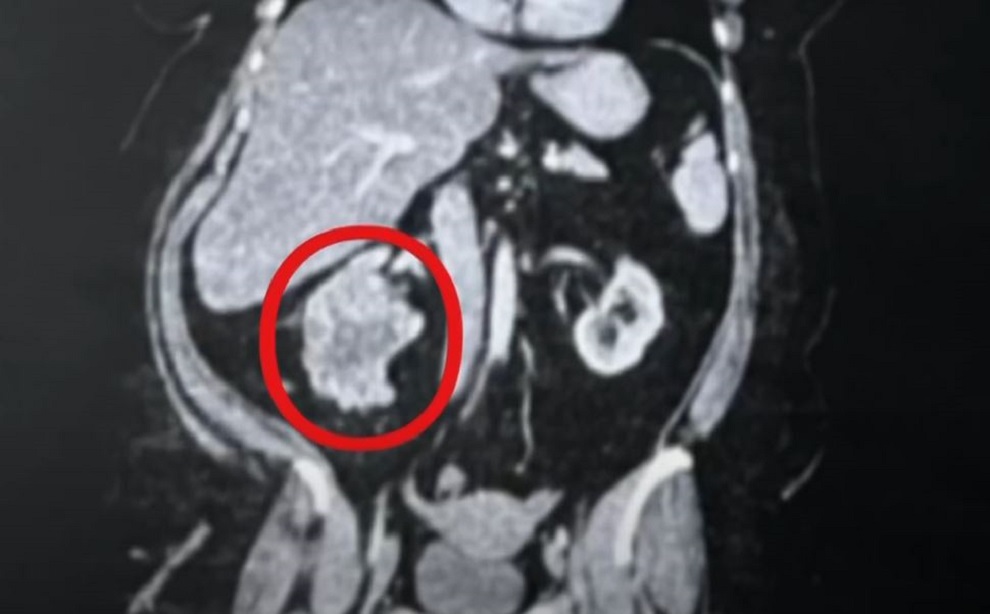

Αυτό που ακολούθησε ήταν μια εξέταση που αποκάλυψε ότι είχε καρκίνο σταδίου 3 στα νεφρά και έναν όγκο στο δεξί της νεφρό, στο μέγεθος μιας μπάλας του μπέιζμπολ.

Σύμφωνα με την Daily Mail όταν έφτασε στο νοσοκομείο Saint Francis στην Τάλσα, αρχικά υποβλήθηκε σε εξέταση. Μια νοσοκόμα τη ρώτησε πού πονάει και τότε ανέφερε ότι ένιωθε πόνο και στην περιοχή του στομαχιού της. Το προσωπικό πίεσε την περιοχή, προκαλώντας της έντονο πόνο, γεγονός που τους έβαλε σε υποψίες και στη συνέχεια η ασθενής έκανε αξονική τομογραφία, η οποία αποκάλυψε τον καρκίνο στο δεξί της νεφρό.